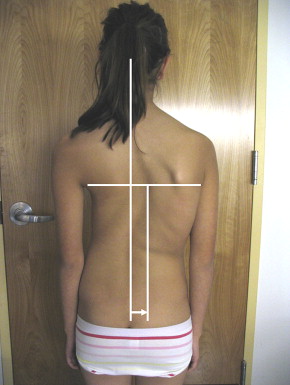

👉 وبالتالي، قد يلاحظ الأهل علامات مثل:

- عدم تساوي الكتفين

- ميلان في الجسم

- اختلاف مستوى الحوض

سابعًا: ما هو Rib Hump (بروز الضلوع)؟

في بعض الحالات، قد يلاحظ الأهل بروزًا في أحد جانبي الظهر عند الانحناء للأمام.

📌 هذا يسمى Rib Hump، ويحدث بسبب دوران الفقرات وليس فقط بسبب الانحناء الجانبي.

👉 لذلك، فهو علامة مهمة على وجود اعوجاج ثلاثي الأبعاد وليس مجرد مشكلة شكلية.